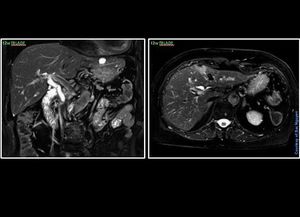

MR Abdominal Imaging @ FastBlade (fblade) @ Siemens 1.5T Aera For those who routinely use blade approach for abdominal imaging, I strongly recommend to try FastBlade and compared that to the standard Blade. My experience is that the FastBlade is better in everyway. Available on the siemens user tree on software E11c. #s_mri #siemens #mri #fblade #abdominal_liver